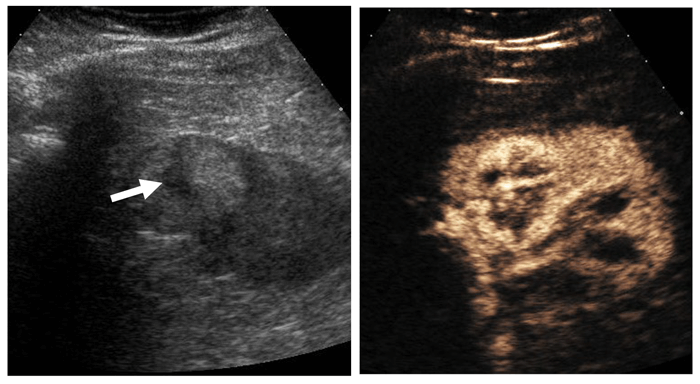

Contrast enhanced ultrasound (CEUS) with microbubble injection is an emerging tool in small renal mass characterisation and serves to identify abnormal vascularity. Although CEUS cannot differentiate malignant from benign renal masses, for instance RCC from oncocytoma, CEUS can reliably differentiate simple cystic lesions from solid vascularised lesions (Figure 4) [6]. CEUS is particularly useful for assessing septal vascularity within complex cystic lesions and problem solving in cases where CT / MRI assessment of small renal lesions proves indeterminate.

Figure 4: Mildly hyperechoic renal lesion on US (left).

Avid enhancement following microbubble injection (right).

Courtesy of Dr Cherian George, UHNM NHS Trust.